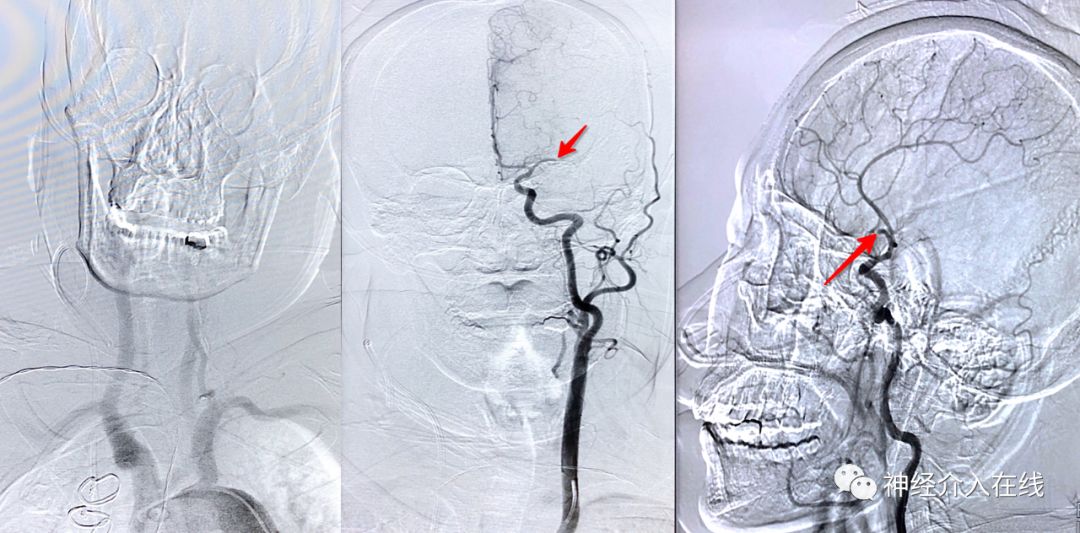

病例继续,没有全麻条件,局麻下主动脉弓喷了一枪(患者躁动,显示不清),直奔主题,术前造影:LMCA M1 主干闭塞,根据术前病史和既往史、手术史,患者心源性栓塞的病因诊断似乎毋庸置疑啦。